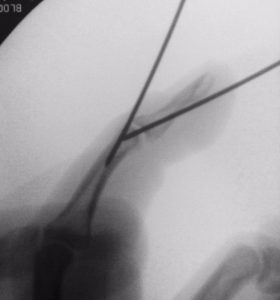

Cuando las radiografías muestran una fractura-arrancamiento, aún es posible el tratamiento conservador.  Sin embargo, otras veces es necesario el tratamiento quirúrgico, para lo que se pueden usar agujas, pines,… en función del tipo de lesión (Figura 5).

Figura 5 - Radiografía postoperatoria de fractura-avulsión en dedo en martillo.